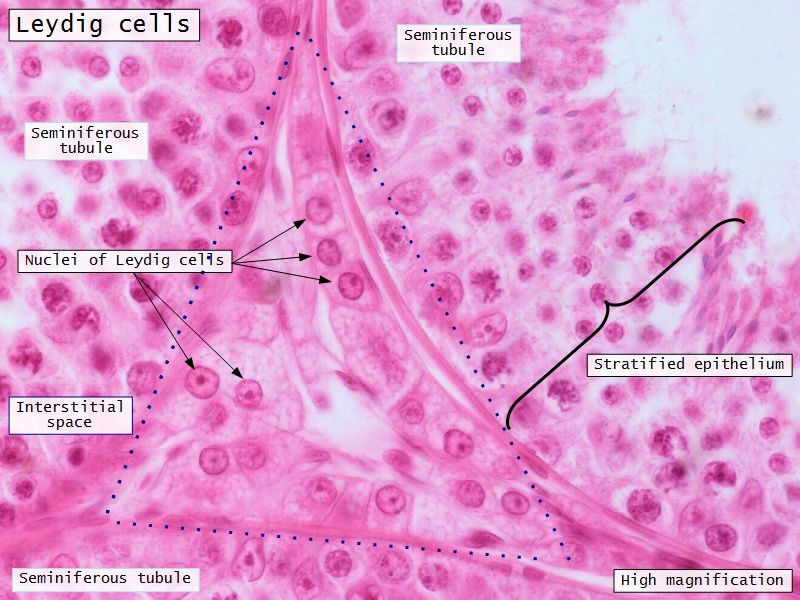

Leydig cells

- Interstitial cells

- Surrounded by rich AVL

- Large round - polygonal shape with clear cytoplasm

- Large central nucleus

- Endocrine - testosterone